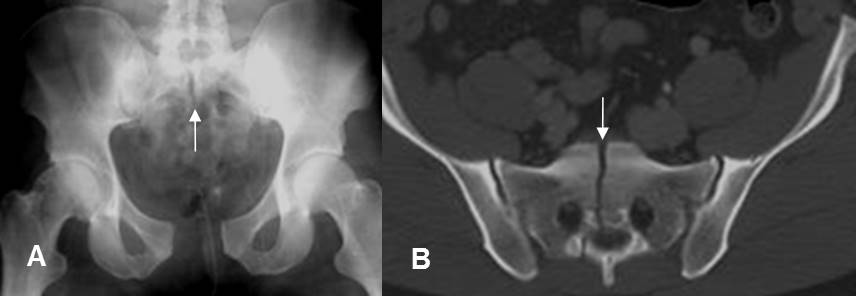

Fig 163. Diastasis.

A: Rx AP y B: TAC axial. Diastasis de la sínfisis púbica, conservándose íntegras las articulaciones sacroiliacas. Hay fractura vertical del sacro, sobre la línea media.